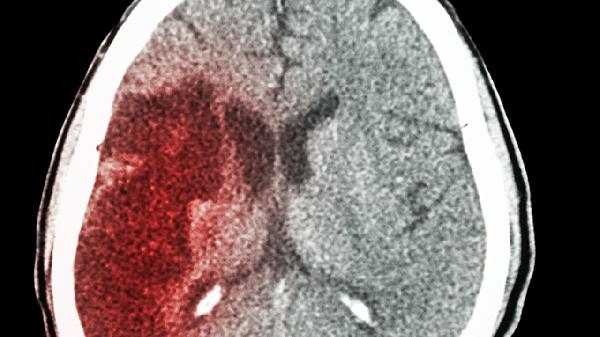

急性脑出血可能由高血压、脑血管畸形、脑淀粉样血管病等原因引起。急性脑出血通常表现为突发头痛、呕吐、意识障碍等症状,需及时就医治疗。

高血压是急性脑出血最常见的原因。长期高血压会导致脑内小动脉硬化,血管壁弹性下降,在血压突然升高时容易破裂出血。高血压性脑出血多发生在基底节区,患者可能出现偏瘫、言语不清等症状。治疗需立即控制血压,可使用硝苯地平控释片、卡托普利片等降压药物,同时配合脱水降颅压治疗。

脑血管畸形包括动静脉畸形、海绵状血管瘤等先天发育异常的血管病变。这些异常血管壁薄弱,在血流冲击下容易破裂出血。脑血管畸形引起的脑出血常见于年轻人,出血部位多在大脑半球。患者可能出现癫痫发作、局灶性神经功能缺损等症状。确诊后需考虑手术切除或介入栓塞治疗。

脑淀粉样血管病多见于老年人,是由于β淀粉样蛋白在脑血管壁沉积导致血管脆性增加。这种原因引起的脑出血好发于脑叶,患者可能出现认知功能障碍、精神行为异常等表现。目前尚无特效治疗方法,主要采取控制血压、预防再出血等对症支持治疗,必要时可使用甘露醇注射液降低颅内压。